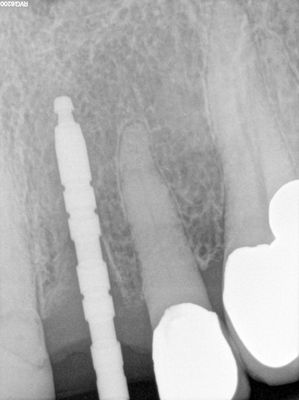

atraumatic exo 21, labial plate intact, osteotomy underprepared in ideal position, soft bone, implant placed at under 20Ncm of torque but ISQ tested over 70. decided to immedaite load, loaded with temp crown out of occlusion